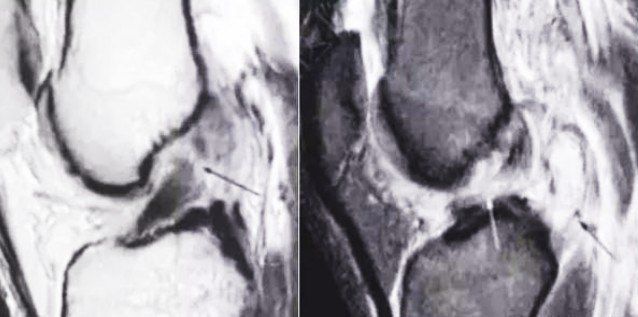

做完前交叉韧带 Acl 重建手术后韧带 变 啥样

做完前交叉韧带 Acl 重建手术后韧带 变 啥样 Vk32